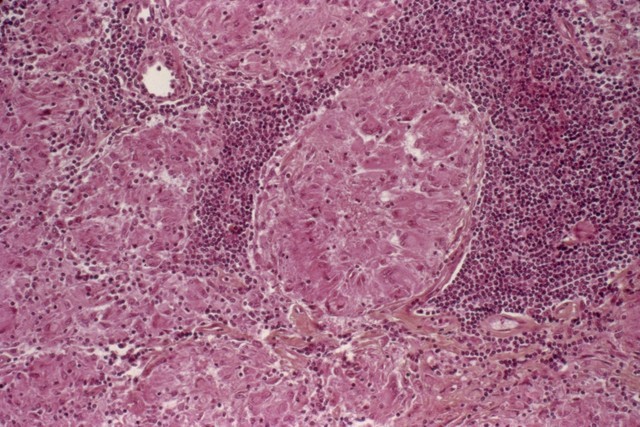

第二、淋巴结增大!淋巴是猪的免疫功能系统。一般出现病毒性感染,淋巴都会有病变,但是非瘟主要是增大、水肿以及整个淋巴结出血,形态类似于血块!